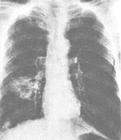

檢查肺心病

胸片右圖示慢性氣管炎,肺氣腫,肺心病。雙側肺過度充氣,

肋間隙增大,

雙肺紋理粗大,

心臟呈垂滴形。

肺動脈段突出。